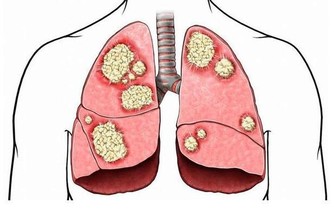

自2010年2月4日,因喉部總有異物感和頸部淋巴結腫痛看病。醫生給我做了淋巴結針吸,及甲功全項檢查。結果為甲狀腺球蛋白為351.正常值應該是0.針吸結果為淋巴有外癌細胞。考慮為轉移癌。2010年2月20日,在北京協和醫院確診為:甲狀腺癌晚期,已經轉移至肺部。CT胸片為有大量結節組織。多為5毫米以下為轉移癌。

2010年3月1日,在醫院住院, 檢查頸部彩超,左側多發結節,大部分鈣化。右側甲狀腺部位有1.6×1.3 cm的腫瘤。2010年3月8日,在醫院行甲狀腺右側全切及左側淋巴清掃術。手術過程中斷紮帶狀肌,斷扎甲狀腺動靜脈,斷扎甲狀腺側韌帶,斷開左側胸鎖乳突肌,斜方肌,斷扎頸外靜脈及頸深筋膜。斷扎頸叢神經根行淋巴清掃術。術後病理結果為甲狀腺高分化乳頭狀癌,淋巴2/5轉移。術後15天進行了碘131治療,現在正在進行第四次碘131隔離治療。